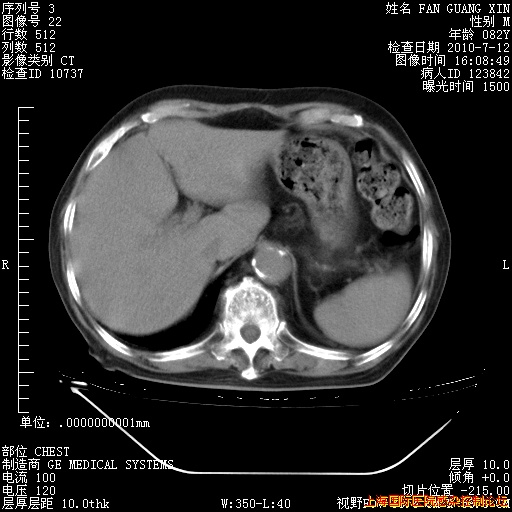

今天CT

回复